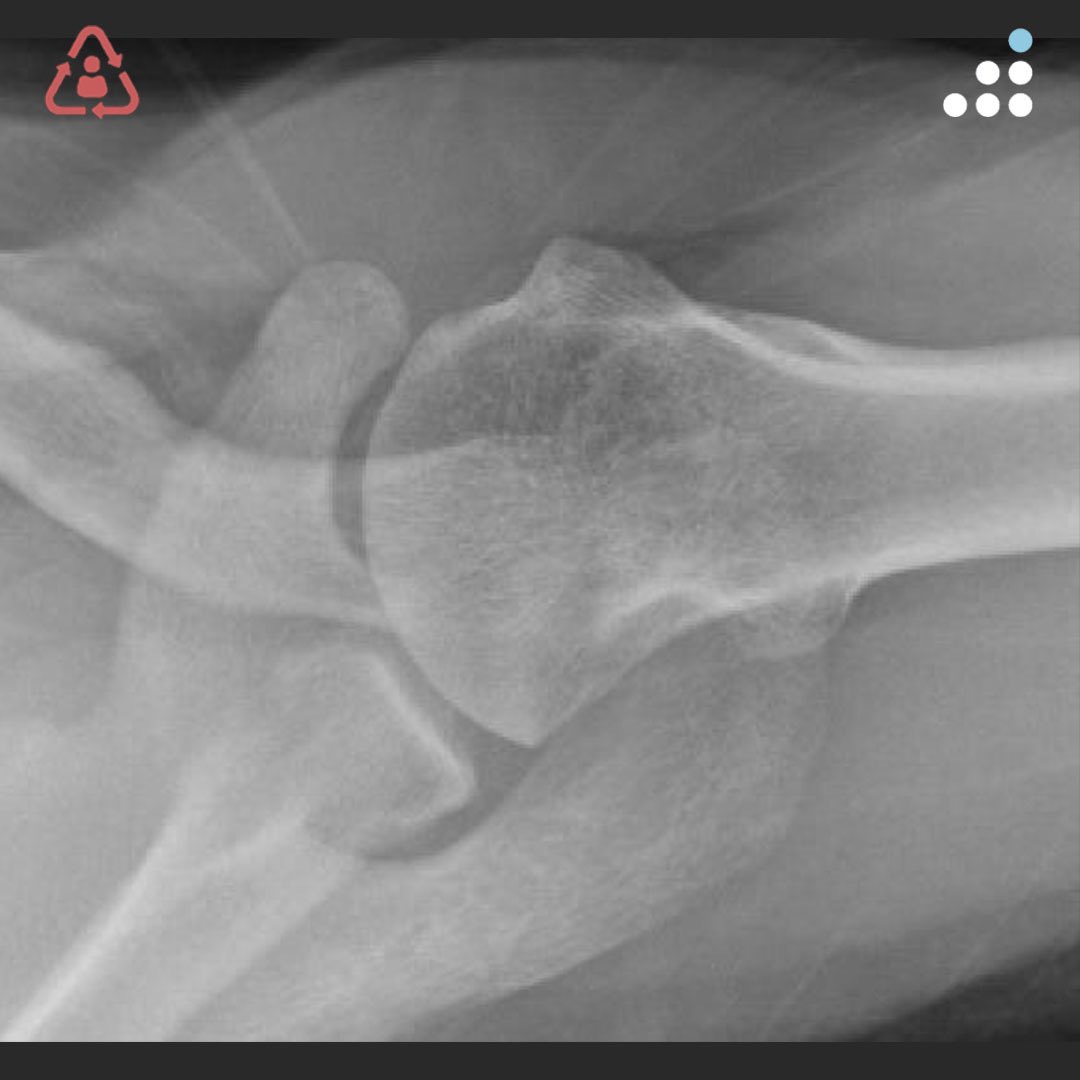

@orthobullets If there is still some cartilage left on the reverse Hill Sachs I’ve had some luck with doing a humeral head osteoplasty. I’ll use allograft chips or cement to backfill the defect after I tamp up articular surface and then try to get everything repaired especially in young pts